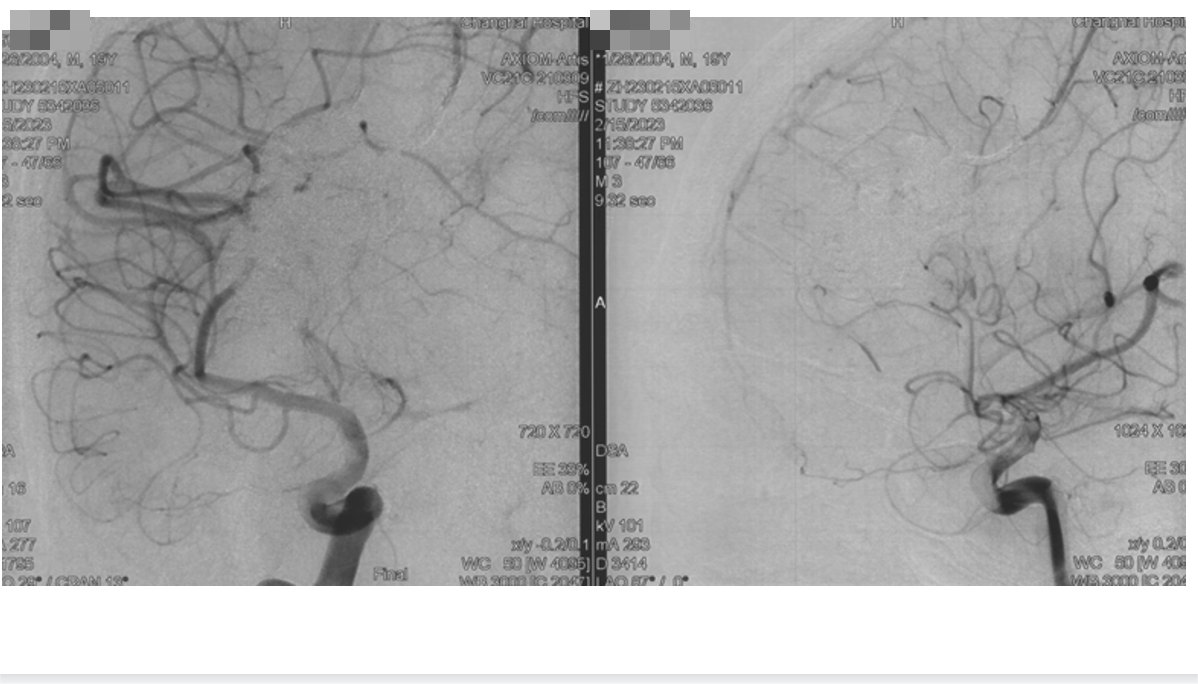

造影

旋转造影

工作角度造影

微导管造影